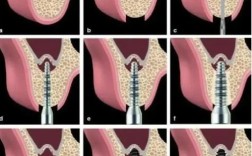

种植体植入与骨整合模拟图

植骨术后3-6个月,当骨密度达到种植标准(如骨量≥50%),需模拟种植体植入过程及预期效果:

- 种植体位置设计:基于生物力学原则,确定种植体的植入角度(如避免近中倾斜>15°)、深度(种植体平台与牙槽嵴顶平齐或位于骨下0.5mm),以及与邻牙的距离(≥1.5mm),图中可标注“理想种植体长轴”,确保受力方向与咬合力一致。